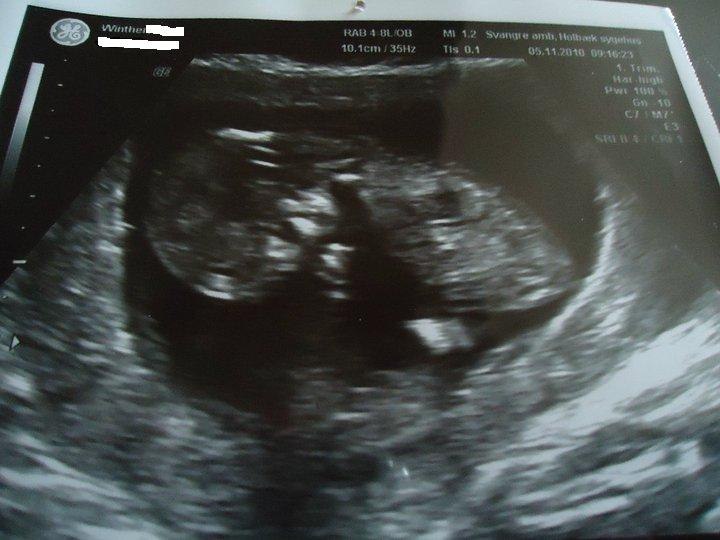

Ved jeg Ikke endnu (; Så den overraskelse har jeg stadig til gode

MEn glæd dig til din første scanning det er en fantastisk oplevelse

Og Stort tillykke med graviditeten ... Det er en skøn følelser når der er liv derinde